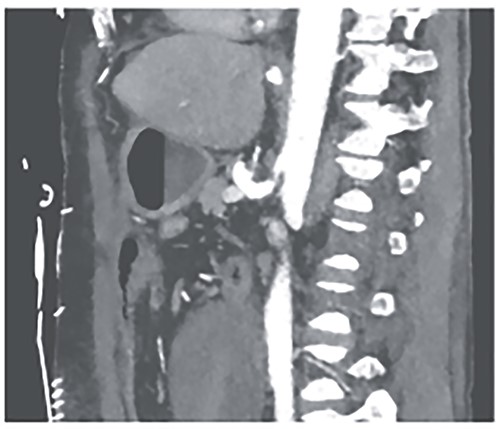

Postoperatively, the patient achieved hemodynamic stabilization in the intensive care unit. On the sixth postoperative day, there was a recurrence of circulatory collapse in addition to relevant bloody discharge through the drains. CT imaging once again revealed an active bleeding of the pancreaticoduodenal artery, which was successfully treated interventionally using coiling (Figs 2 and 3).

Angiography revealing the aneurysm of the pancreaticoduodenal arcade.